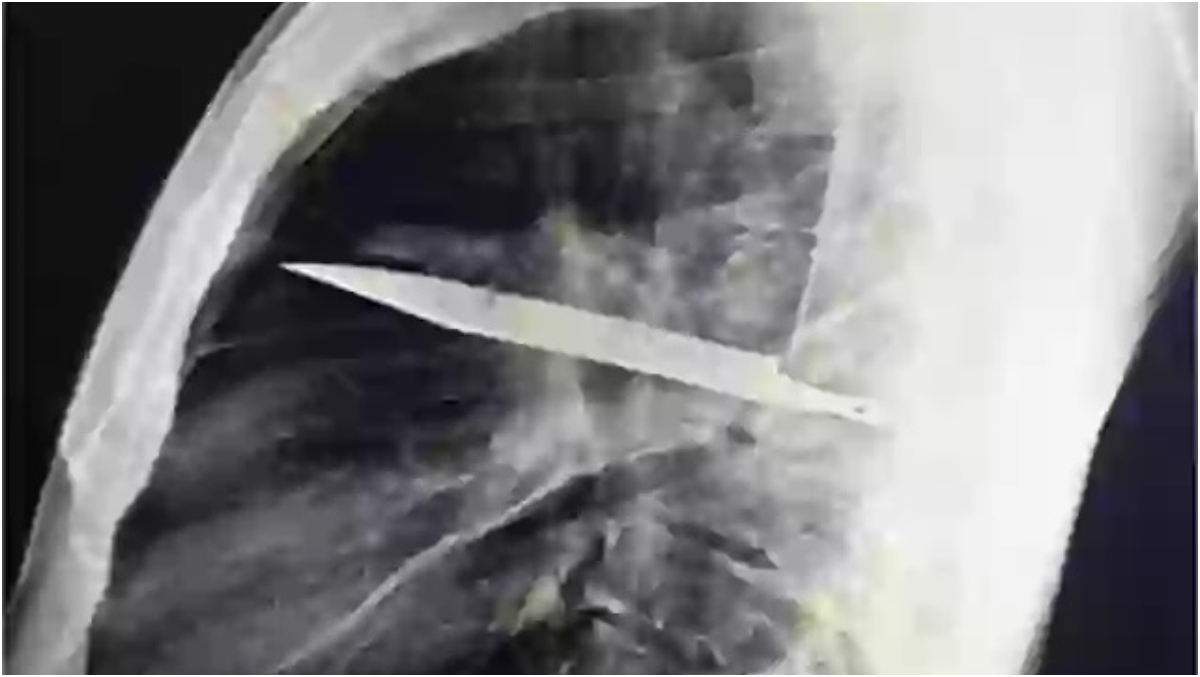

Radiografia a dezvăluit că bărbatul avea un cuțit de dimensiuni considerabile înfipt adânc în piept!

După ce au solicitat o radiografie, a fost găsit un „obiect metalic” imersat, iar medicii și-au dat seama că este o lamă lungă de cuțit, înconjurată de „puroi și țesut necrotic”.

În urma discuțiilor cu pacientul, s-a aflat că acesta fusese înjunghiat în urmă cu 8 ani, iar lama metalică intrase în corp prin umărul drept.